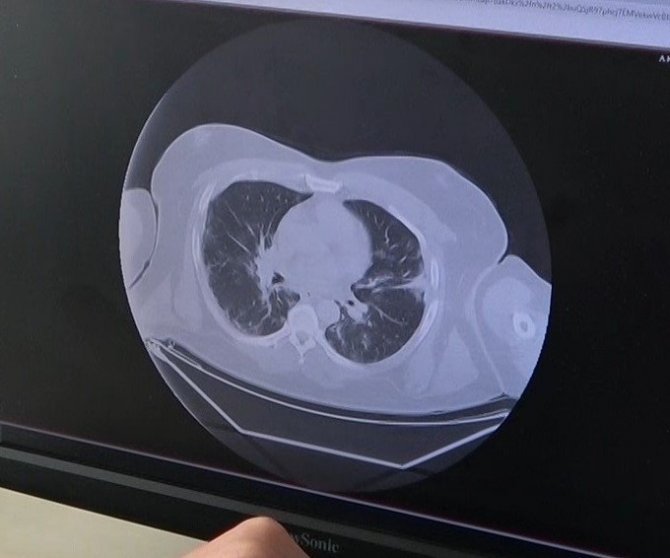

Aşısız hastalarda istemedikleri sonuçlarla karşı karşıya kaldıklarını ifade eden Dr. İlknur Demir, "Şu anda aşısız hastalarımız yoğun bakıma daha fazla yatıyorlar ya da ilk aşıyı olduktan sonra bakanlığımızın önerdiği 2'nci, 3'üncü doz aşılarını yaptırmamış yarı aşılı vatandaşlarımız geliyor. Aşılı bireylerde bu hastalık daha az hasar vererek seyrederken aşısızlarda tüm akciğeri, diğer organları etkileyerek daha ağır seyrediyor. Bu da bizim için açıkçası hiç karşılaşmak istemediğimiz kötü sonuçlara yol açıyor" dedi.

Korona virüsün bulaşmasından sonra 3 gün içinde hızla akciğere nasıl yayıldığını gösteren grafikleri gösteren Dr. Demir, hastanede yoğun bakımda yatış yapanların çoğunluğunun delta varyantı olduğunu söyledi.